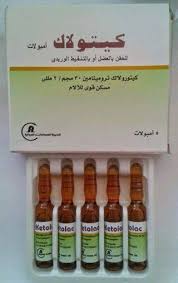

حقنة مسكنة: فولتارين امبولات  او كيتولاك امبول

او كيتولاك امبول